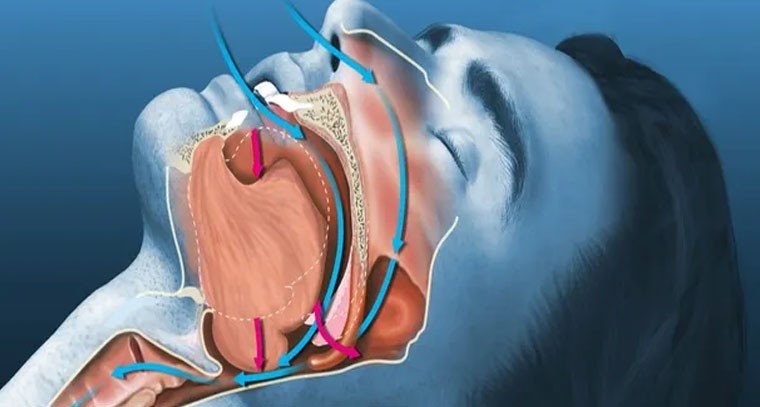

తీవ్ర గురకతో క్యాన్సర్ ముప్పు

Publish : Tue, Oct 15, 2024, 07:29 PM

తీవ్ర గురకతో క్యాన్సర్ ముప్పు

Publish : Tue, Oct 15, 2024, 07:23 PM